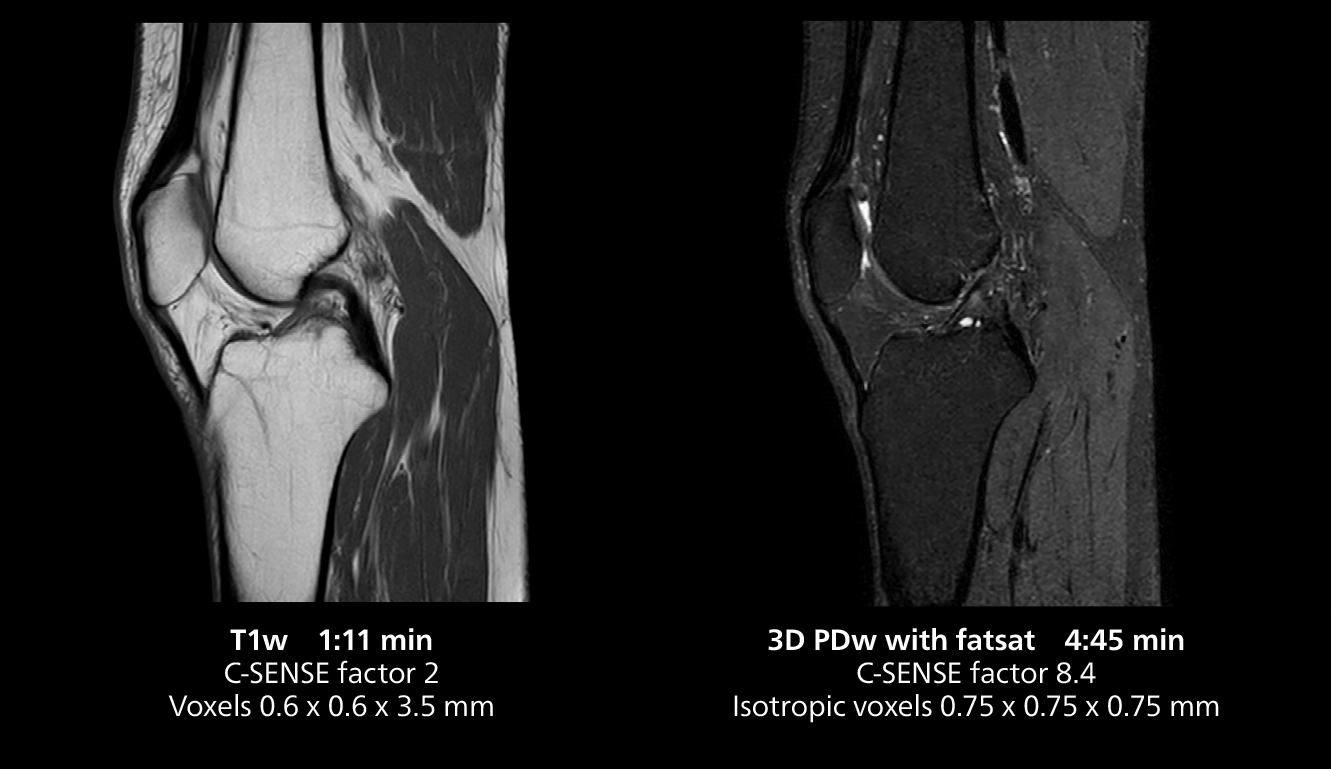

3D knee imaging

The isotropic high resolution 3D sequence in this MRI case allows for reformatting to obtain other orientations with high quality. Acquired on the MR 5300 system.

According to Dr. Gellée, the hospital conducts an average of four studies each hour, totaling about 40-45 patients per day on their MR 5300. Studies are read by approximately 50 radiologists in the Bordeaux area. Dr. Gellée is especially satisfied with the image quality of the MR system. "I obtain higher image contrast and more anatomical precision than I was used to,” she says. “When I am able to choose, I request that studies be done on this system, because I get better anatomical image quality. For example, in the knees, I can get great images of the meniscus. To me, it looks as pretty as 3T.”

“We have more speed in 3D sequences,” Dr. Gellée states. “With Compressed SENSE, we can replace two or three 2D scans withone high-quality 3D scan. High quality additional orientations are then obtained by post-processing of the 3D data set, thus saving scanning time.”